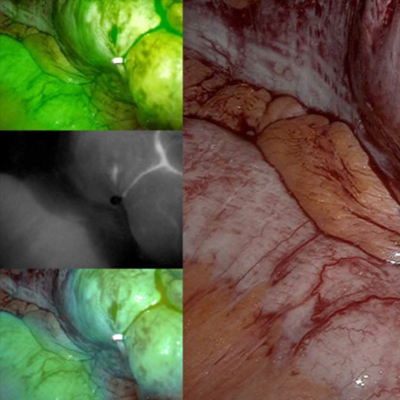

La tecnología de 4 CMOS 4K mejora la visualización en tiempo real, permitiendo un seguimiento preciso del sistema linfático.

La versatilidad del Modo de Luz del sistema VEQTRON® ICG/NIR Twinlight LED-LASER ajusta automáticamente la intensidad de luz según la distancia entre el endoscopio y el tejido. La cámara de mano FluorosQan, con tecnología 4 CMOS, proporciona una visualización detallada de la perfusión tisular en tiempo real durante cirugías abiertas.

El Sistema de Imágenes VEQTRON® ICG/NIR guía cirugías con fluorescencia ICG/NIR, promoviendo resultados más seguros para los pacientes. Esta tecnología mejora la evaluación del flujo sanguíneo y la visualización de tumores, reduciendo complicaciones y acelerando la recuperación.